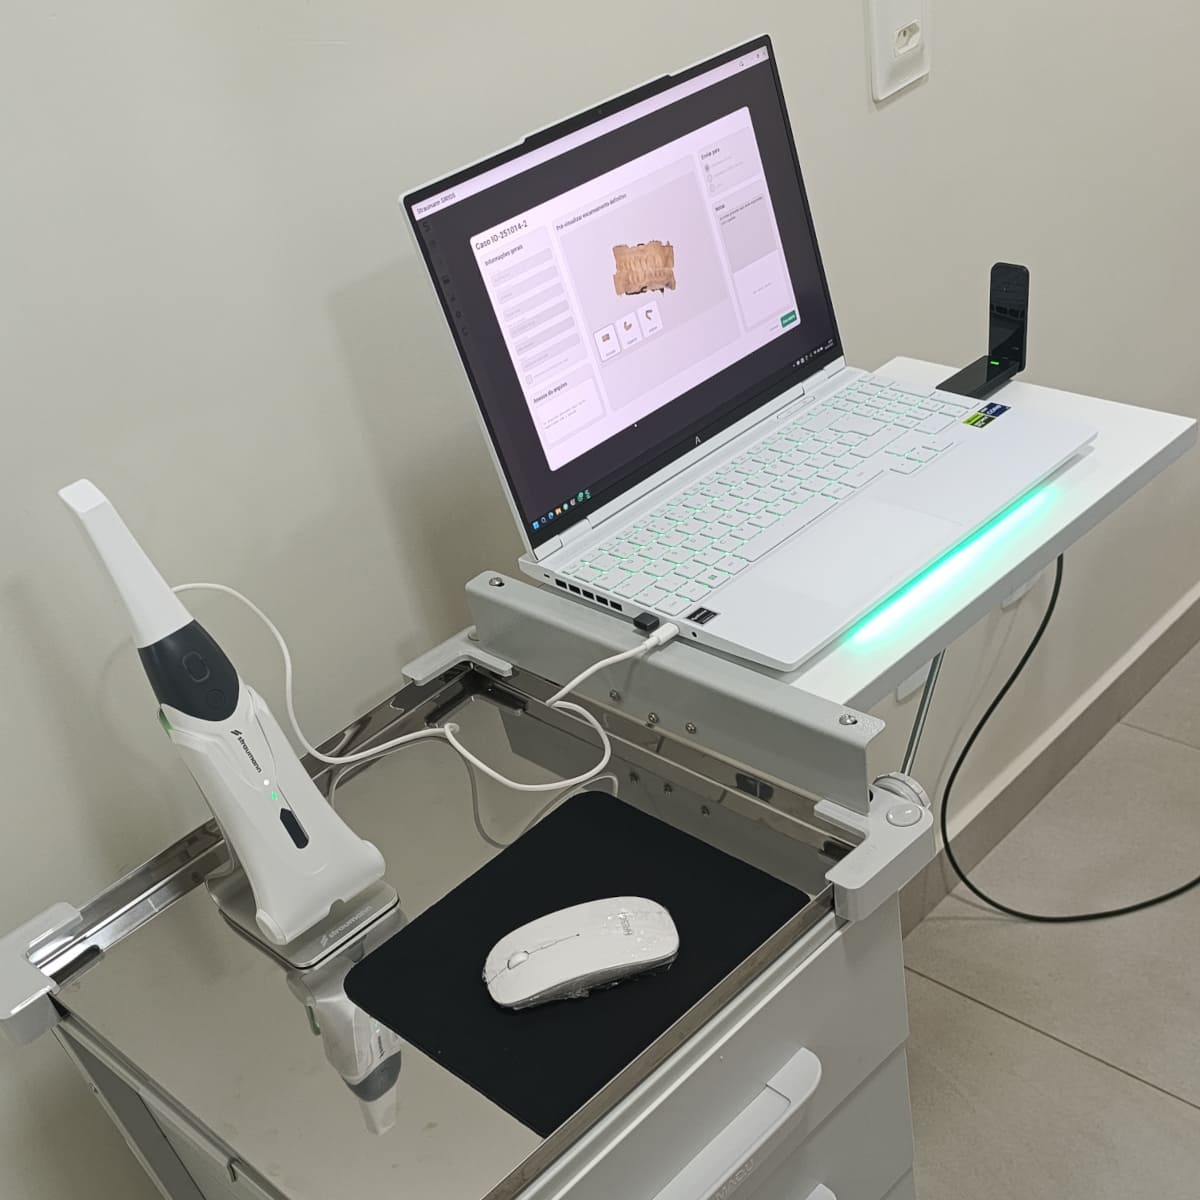

... instala lâminas feitas de porcelana

que serão coladas à superfície dos

dentes preparados para recebê-las ...

... sem dor, sem desconforto

e com muita previsibilidade...